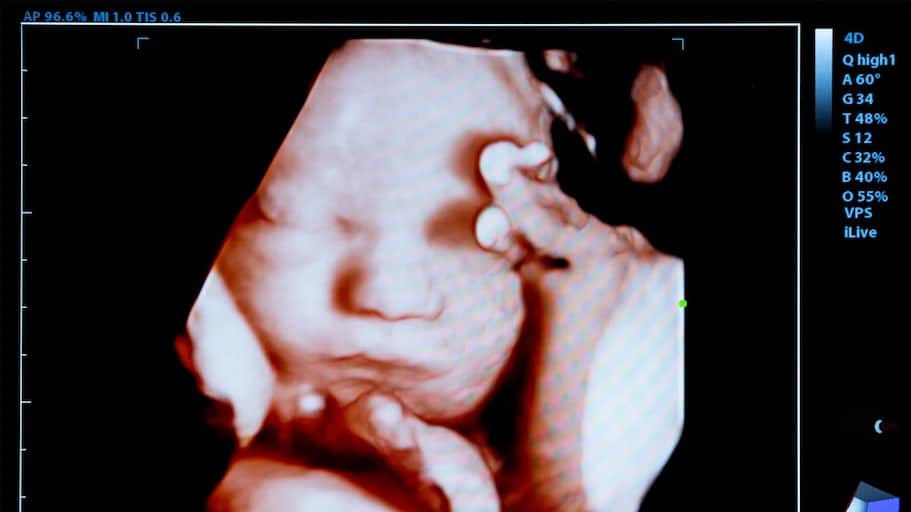

I have often seen the glazed-over look in the eyes of my students when presenting the intricacies and complexities of science, until I show them a picture. Then, their perplexity turns to illumination. In many ways, the obscurities of pregnancy once prevented many from understanding what science already knew about the humanity of the unborn child, until ultrasound technology gave us a clear picture of the little boy or girl developing inside his or her mother’s womb.